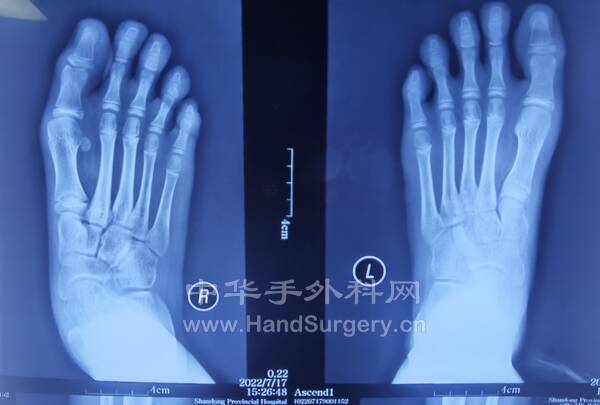

拇趾Chevron+Akin/Scarf+Akin/横行截骨+Akin.第2.3.4趾行Weil手术(图2,3)

3.胫骨延长外固定架术后根据患者情况决定每日拧1圈/2圈,拧3天停1天,1个月复查DR,最终延长的长度以患者行走的舒适度为准!延长的长度约3.5--6cm,外固定架需佩戴4-6个月(图4--7)4.第一,四跖骨短缩的儿童如果想改善外观,可行截骨延长外固定架固定术,需单侧做,时间4-6个月(图8-9)